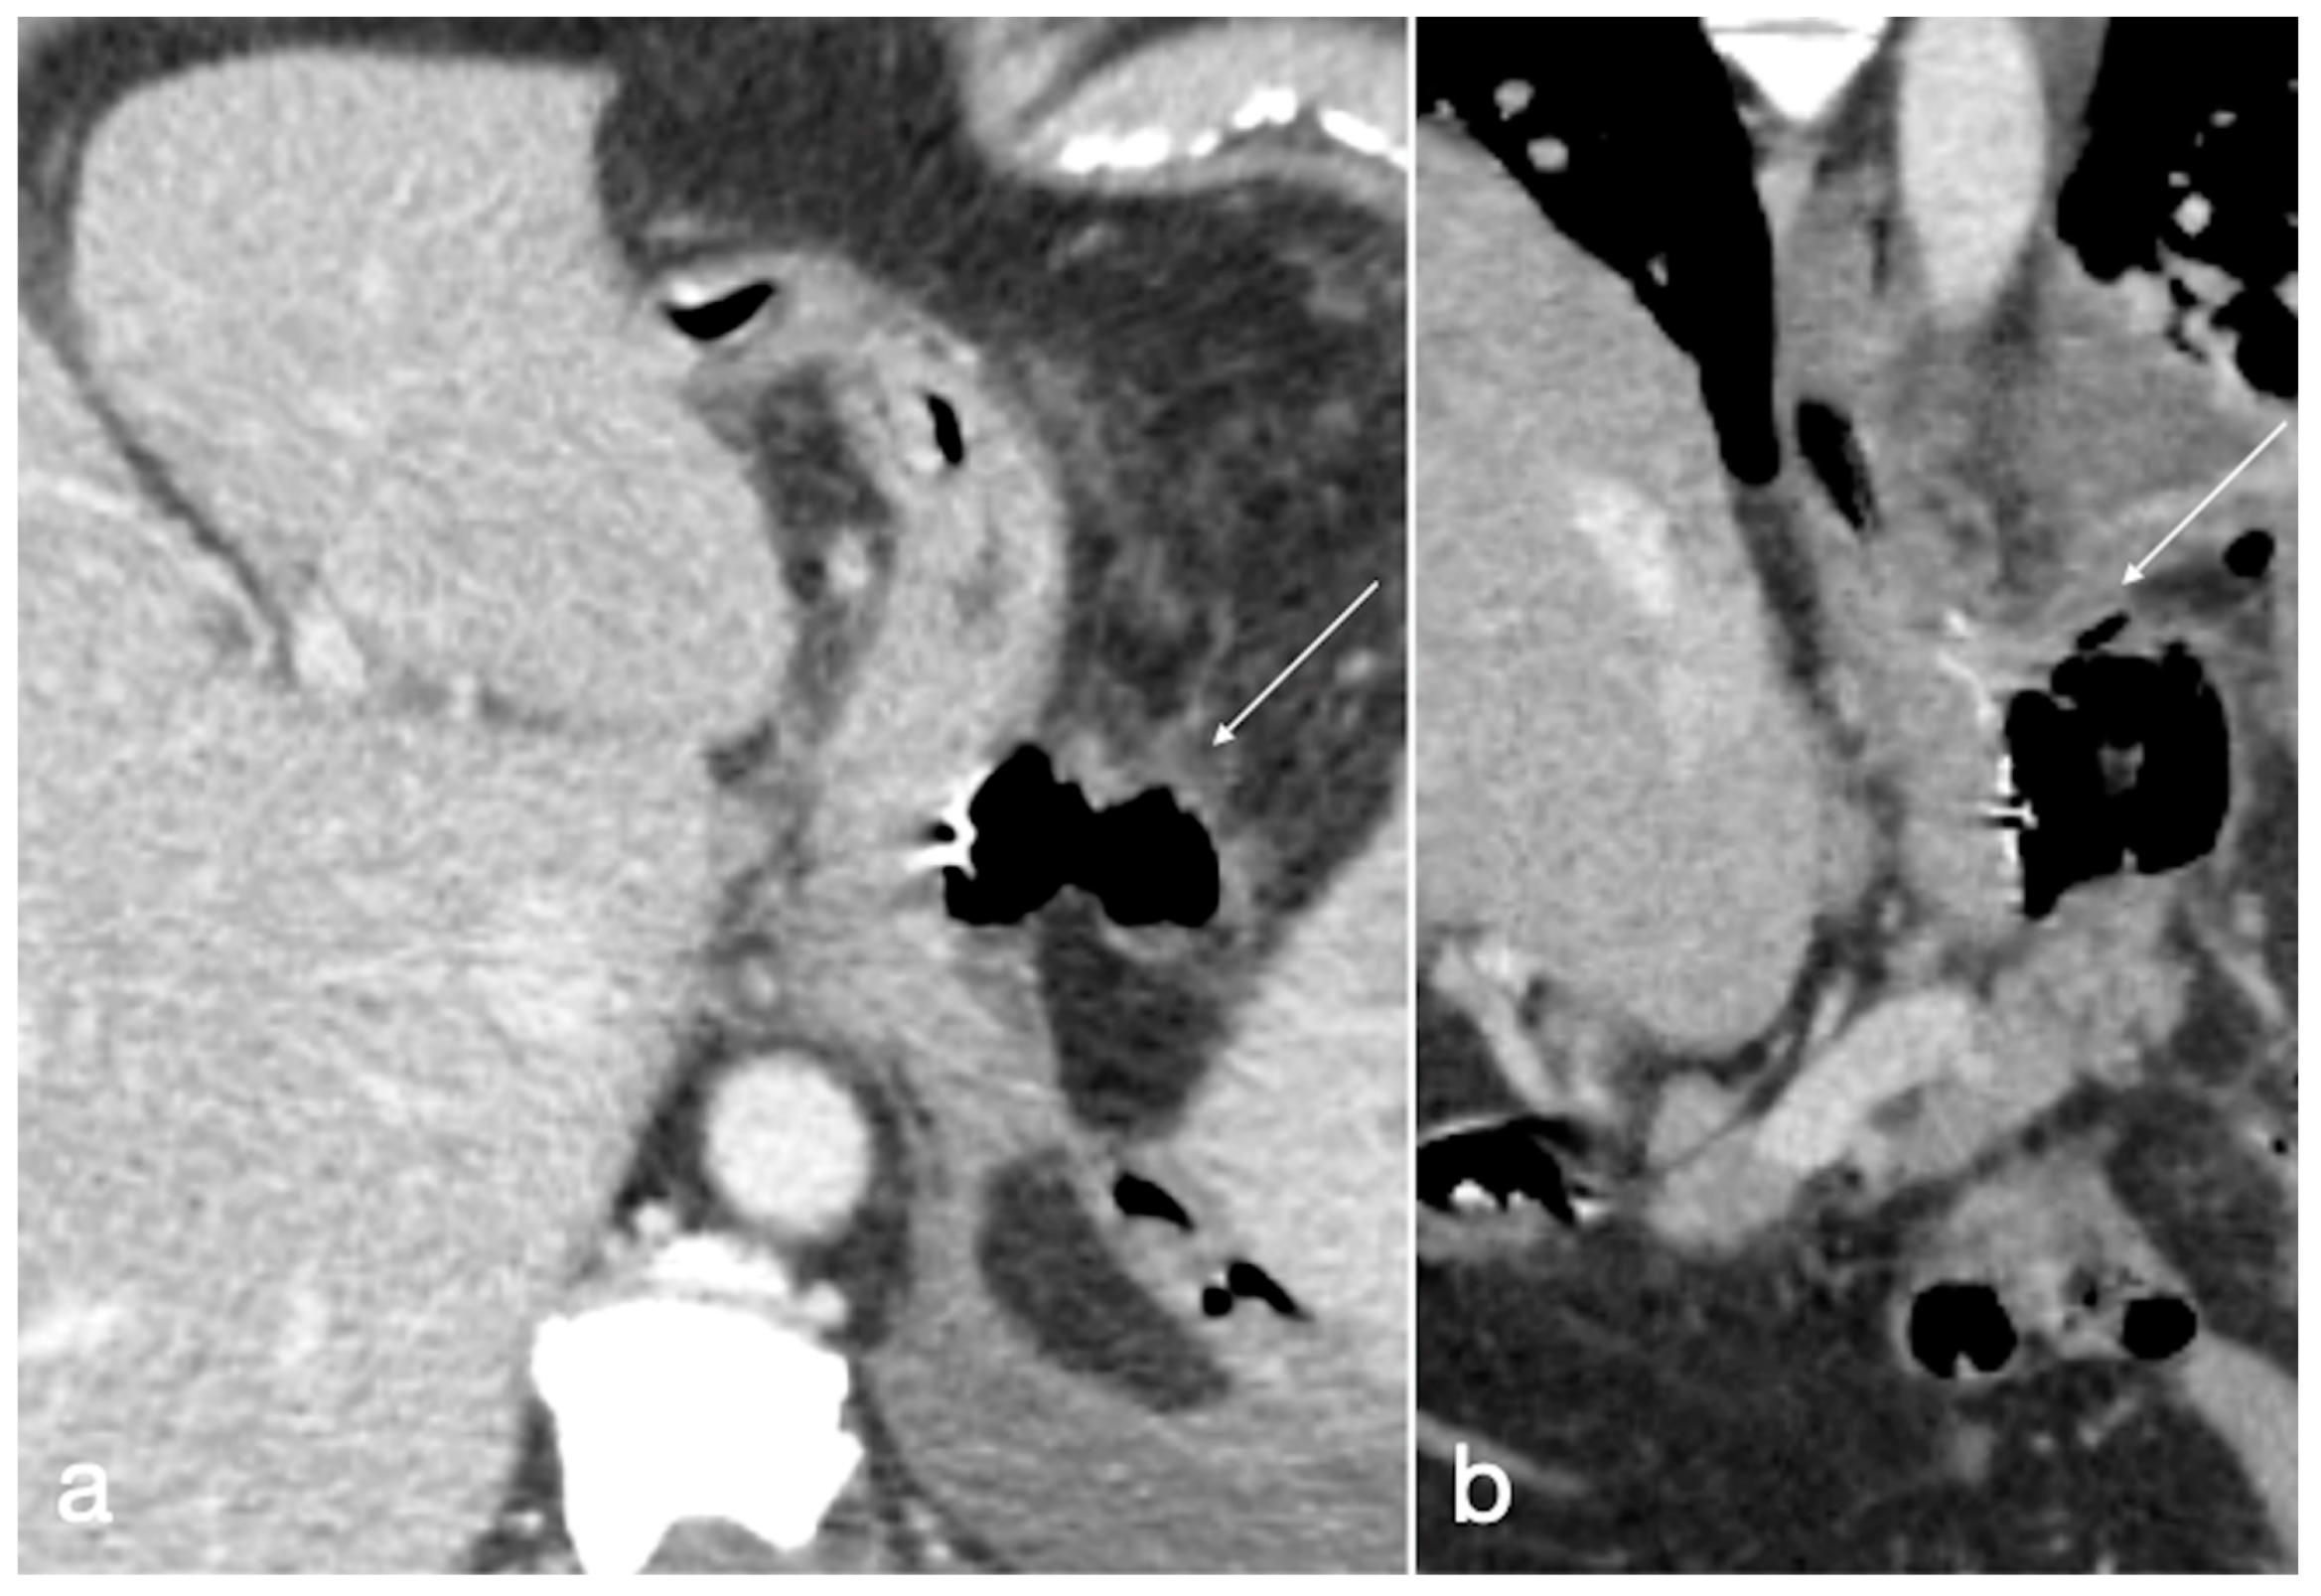

Figure 12. Type I leak after sleeve gastrectomy. See the air collection adjacent to the surgical suture (a, axial view, arrow; b, coronal view, arrow).